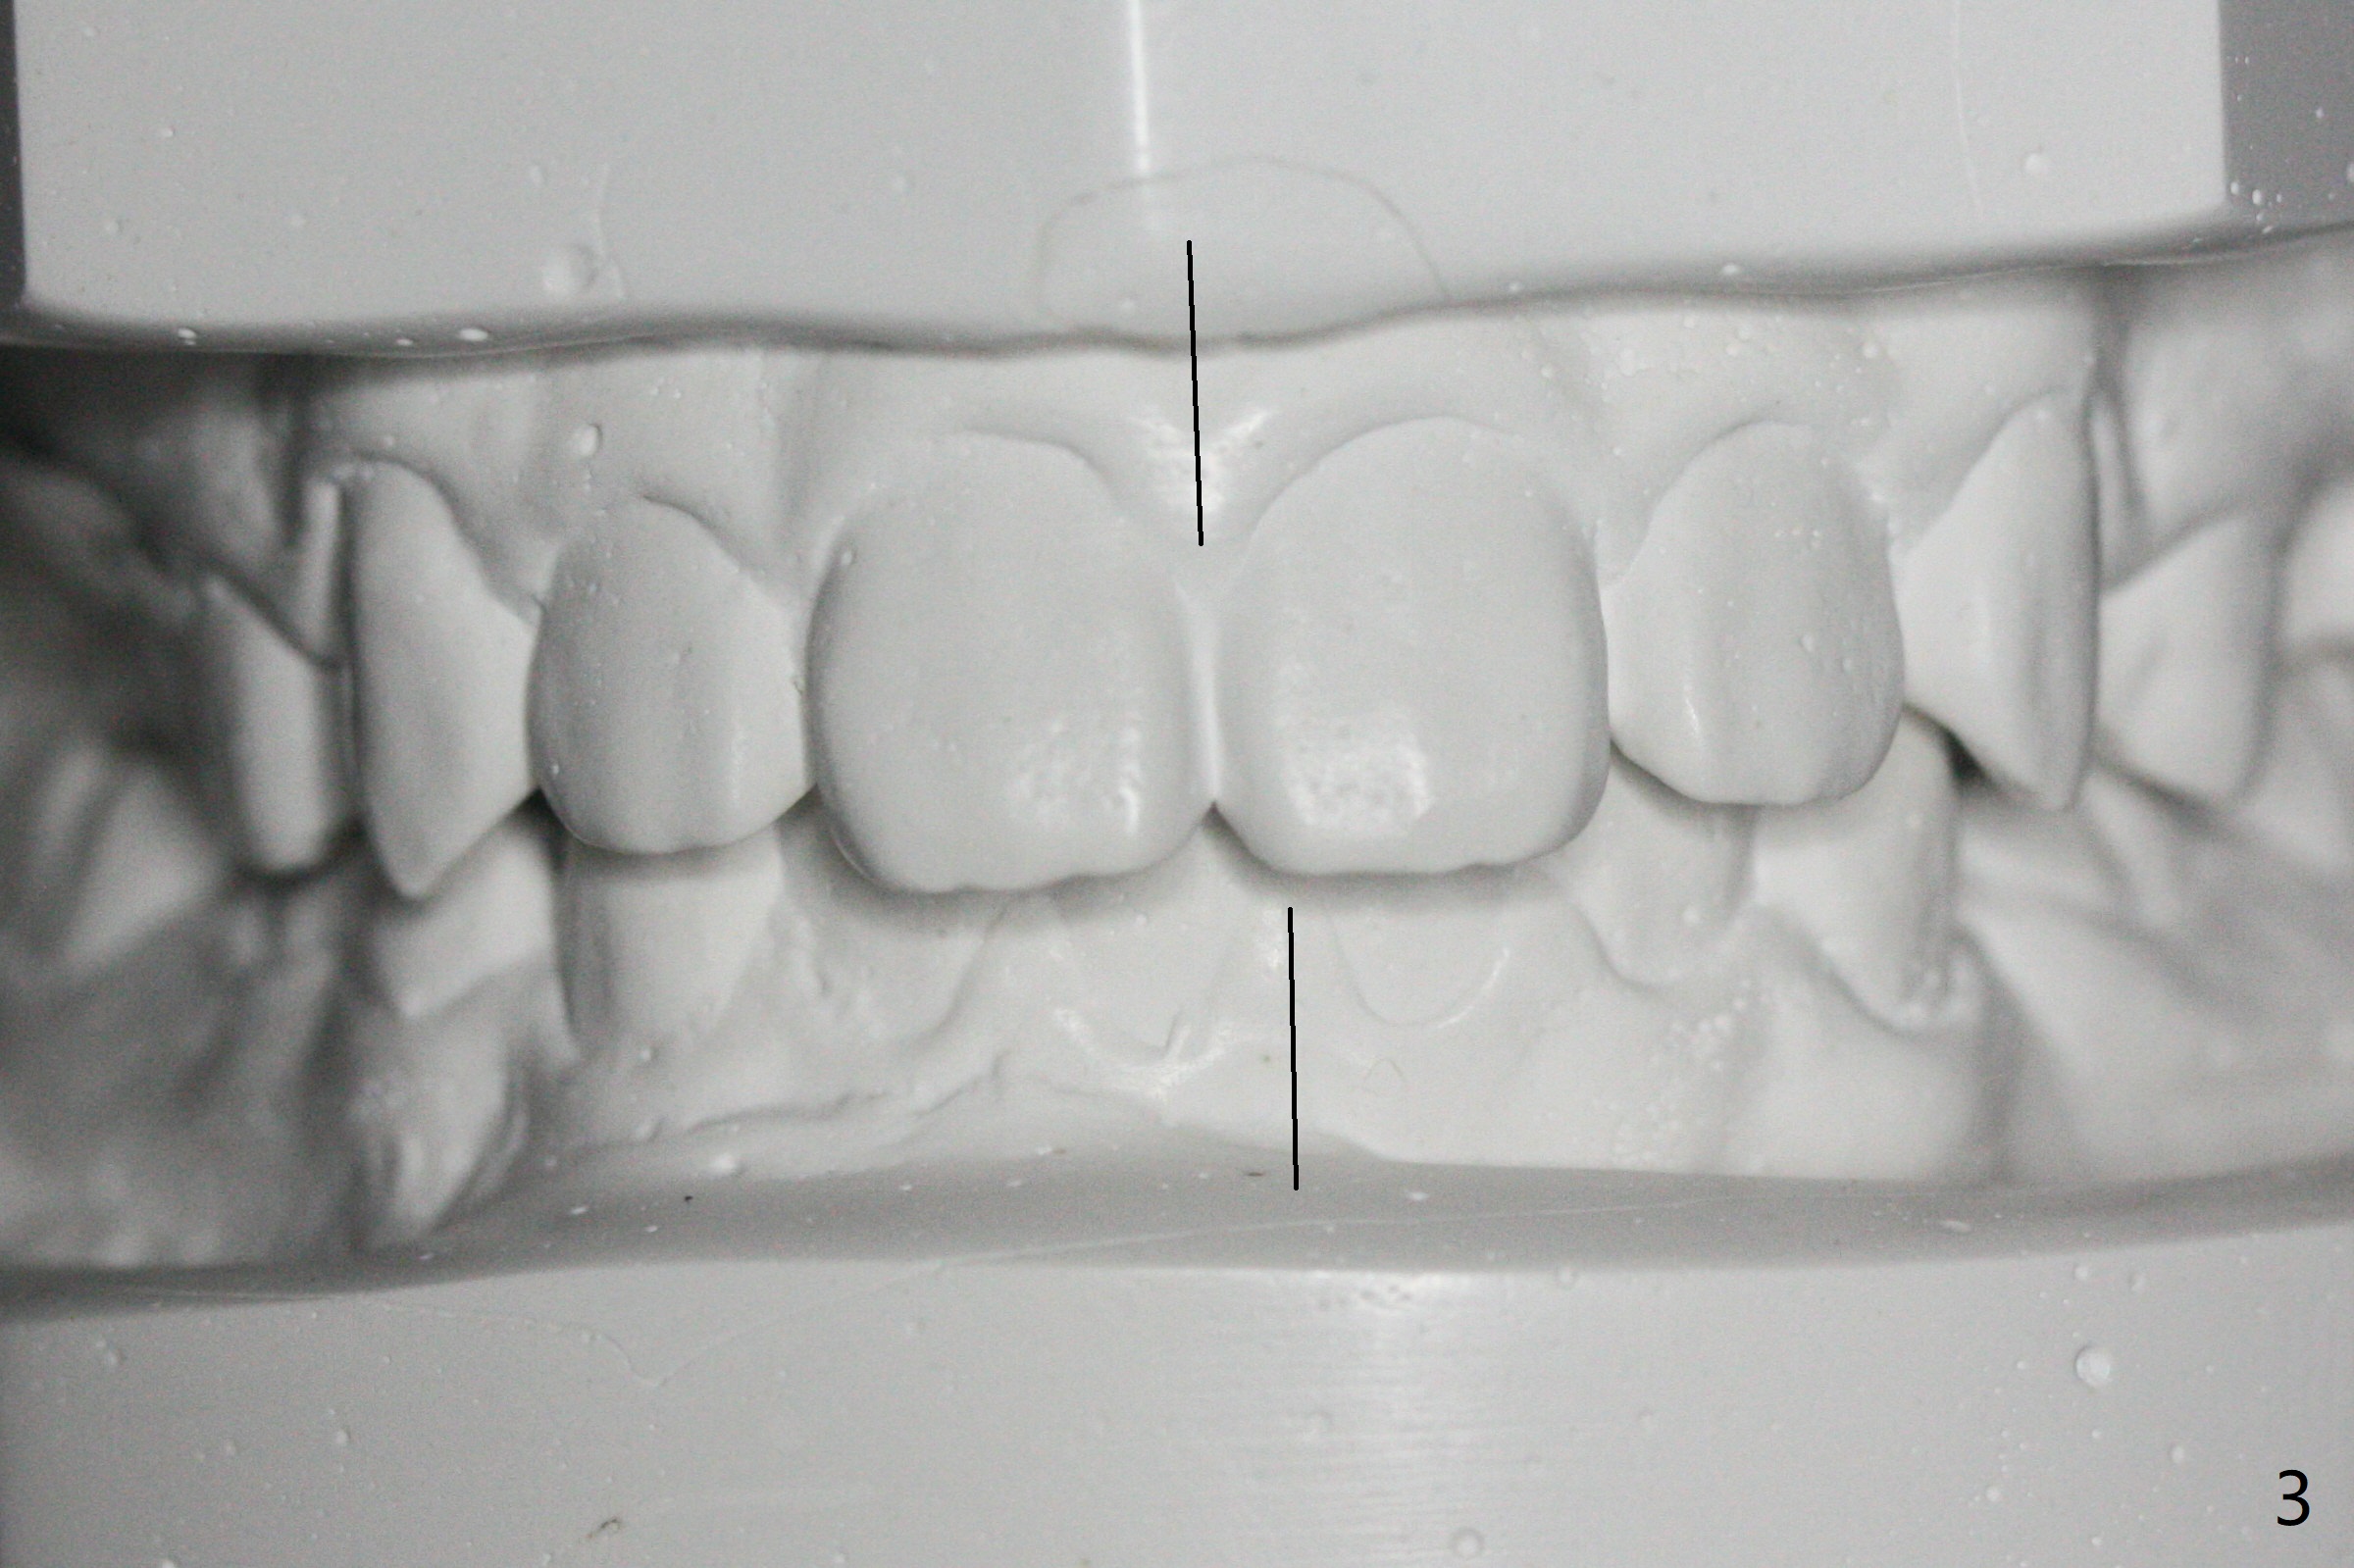

One-year-8-month orthodontic treatment reduces anterior overjet (Fig.1 (double arrows),1', with facial profile improvement), corrects right 1st molar cross bite (Fig.2,2') and dental midlines (Fig.3,3'), closes the diastema between UL3 and 4, extrudes UL5 (Fig.4,5,4',5'), and increases space for future implant at LL4 (Fig.6,6'). In fact large arches with distemata make the treatment possible! Extrusion of UL5 leads to root development (Fig.7, 7' (R)). The increased space at LL4 (Fig.7' *) appears insufficient for an implant.